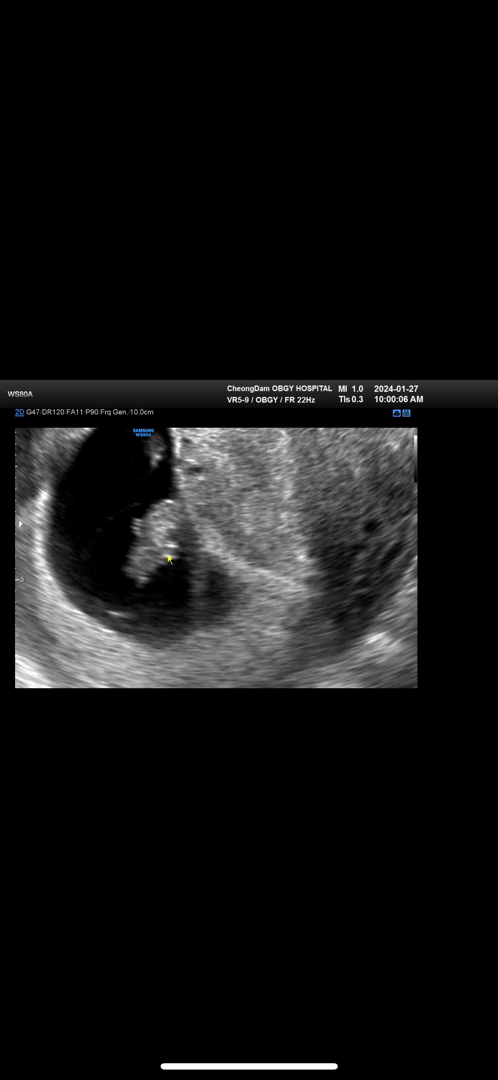

만세! 하는 8주차 젤리곰..👶🏻✨

팔 다리가 생겼다니 너무 신기해서 눈물이 또르르 났네요..🥹